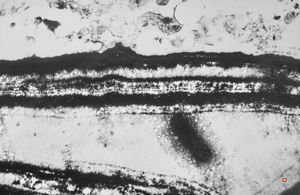

F,23y. | normal oral mucosal epithelium - desmosom